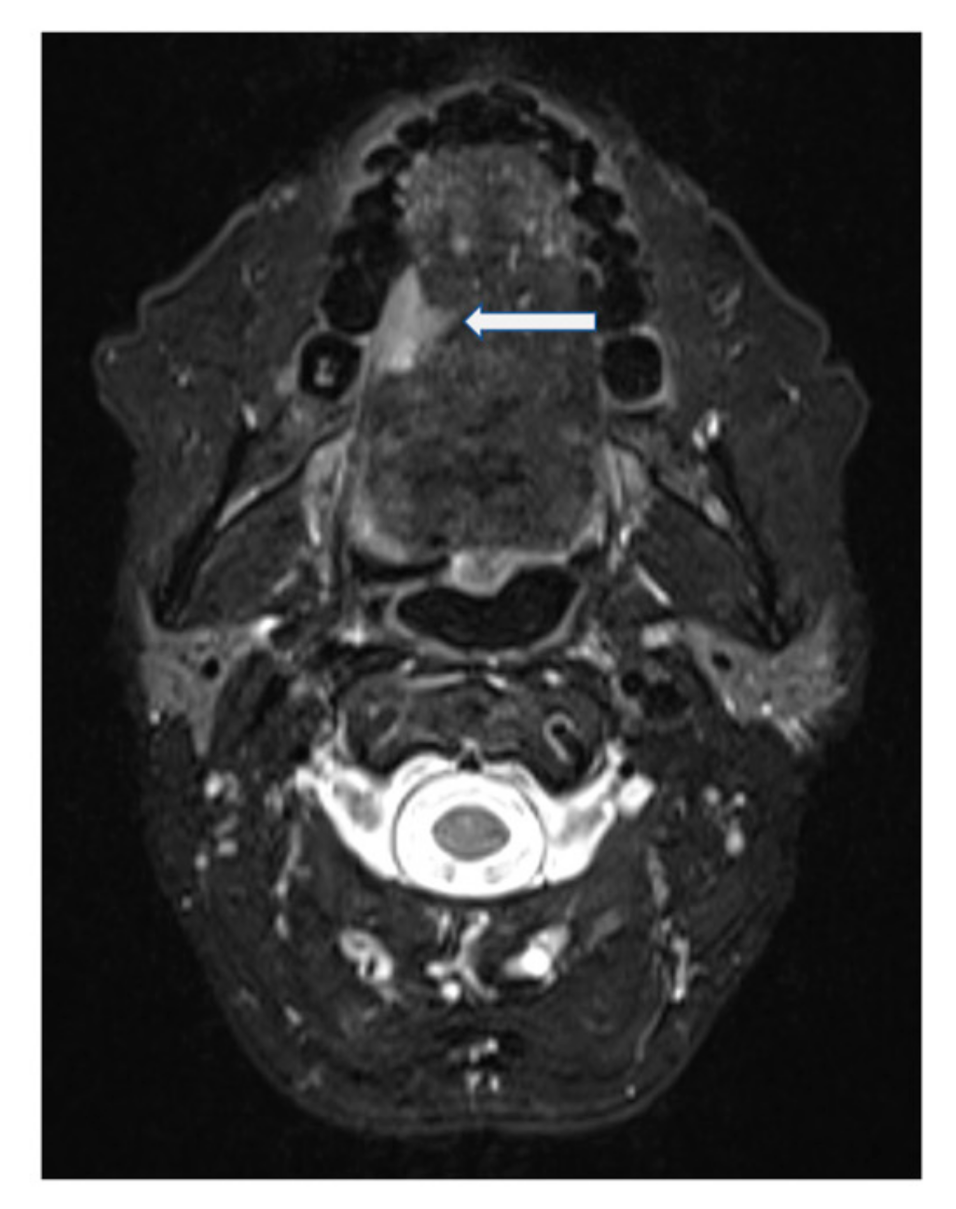

A 53-year-old female was diagnosed with a p16-negative T3N2bM0, Stage IVa SCC of the mobile tongue at an outside institution (Figure 2 and Figure 3). Hemiglossectomy was performed in conjunction with neck dissection of levels I, IIa, III, and IV on the right side. Anterolateral thigh microvascular flap was utilized in reconstruction. Histopathology revealed an SCC with a diameter of 24 mm and with 10 mm depth of invasion. The minimum resection margin was 7 mm on the medial edge of the tumor. She had two metastatic lymph nodes in level IIa with no extranodal extension. The pathological staging was pT2pN2bM0 (Stage IVa). MDTB recommended postoperative chemoradiotherapy.

Figure 3.

T2-weighted fat-suppressed, contrast-enhanced MRI of Case 2 in the axial plane. Squamous cell carcinoma indicated by arrow.